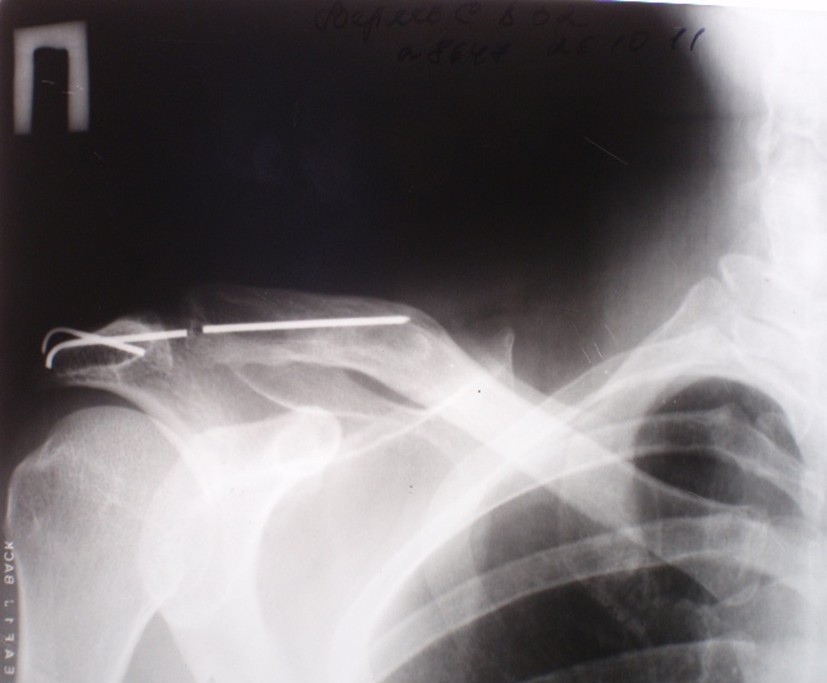

The correctness of our assumptions was confirmed when, after some time, a 40-year-old patient C came to the clinic with complaints of pain in the cervical spine. In 2007, he underwent osteosynthesis of the acromioclavicular joint with two crossed Kirschner wires, which were also not removed. An X-ray examination revealed a fracture of the wires, migration of one of the fragments, and its insertion into the cervical spine (Fig. 4). The patient underwent surgery, and the foreign bodies were removed.

Figure 4. X-ray images of the left shoulder joint and the cervical spine of patient C. Fracture of the pins and migration of one of the proximal fragments.